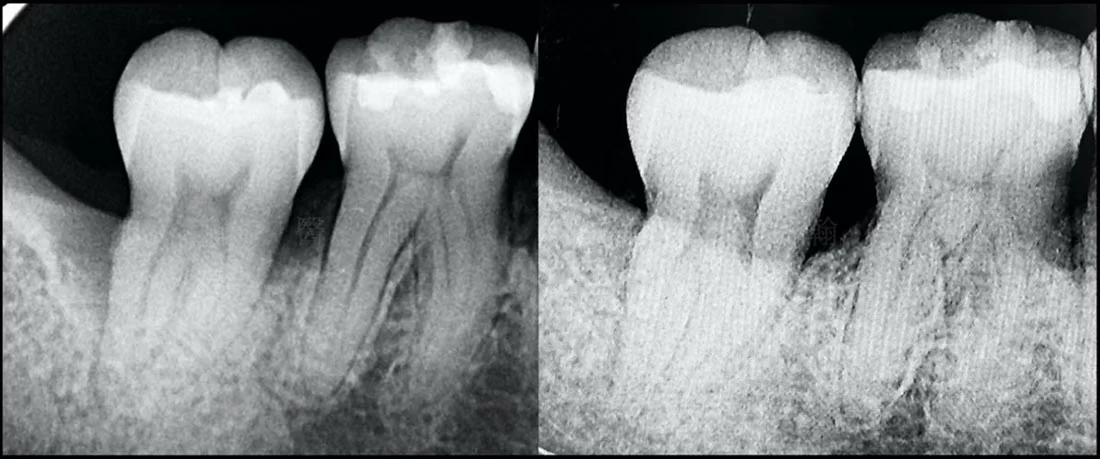

圖1-2

- 左:手術前,可見第二大臼齒遠心側的齒槽骨內缺損與牙結石堆積

- 右:手術半年後,同樣區域從X光片可見骨頭再生的結果